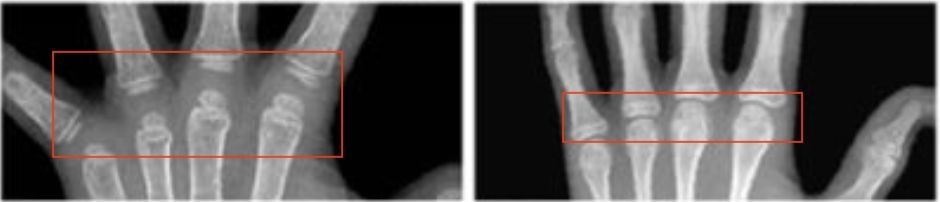

一般都是依据左手的X线结果,虽然判断比较复杂,但是原理基本一致,简单定性说明一下:

一是,依据骨间距。间距越大,生长的空间越大,骨龄越小。

△骨龄小时,骨间距相对较大